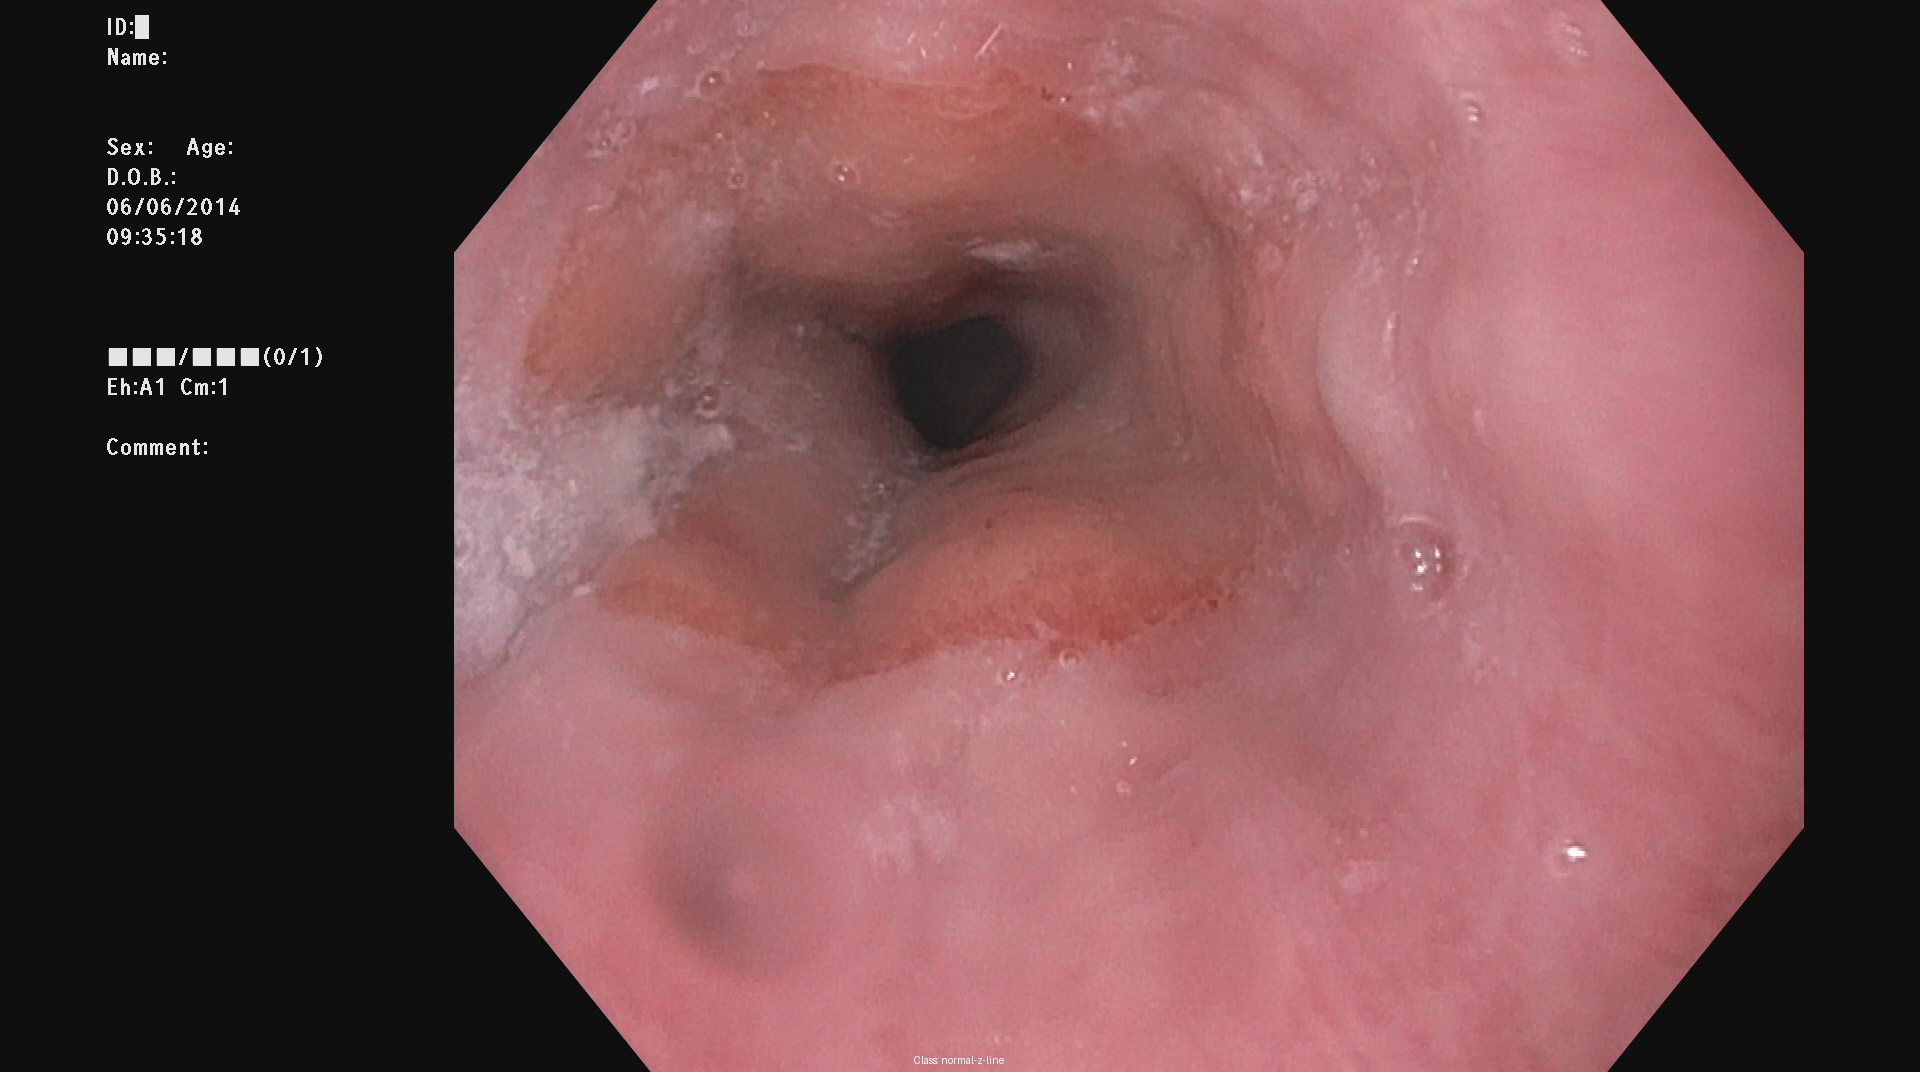

Kvasir dataset serves as a widely recognized resource for research in automated gastrointestinal (GI) disease detection [12]. It contains labeled endoscopic images representing a range of GI conditions, including both healthy and pathological cases. Its diversity in anatomical regions and pathological categories makes it a valuable benchmark for training machine learning models aimed at GI disease classification. The dataset has 8000 images belonging to 8 different classes namely dyed-lifted-polyps, dyed-resection-margins, esophagitis, normal-cecum, normal-pylorus, normal-z-line, polyps, ulcerative-colitis. Figure 1 depicts the sample images from the dataset. Despite its extensive coverage, the dataset poses challenges such as variations in lighting, differences in image quality, and visual similarities between certain categories, which may affect model performance and classification accuracy.

| (a) | (b) | (c) | (d) |

| (e) | (f) | (g) | (h) |